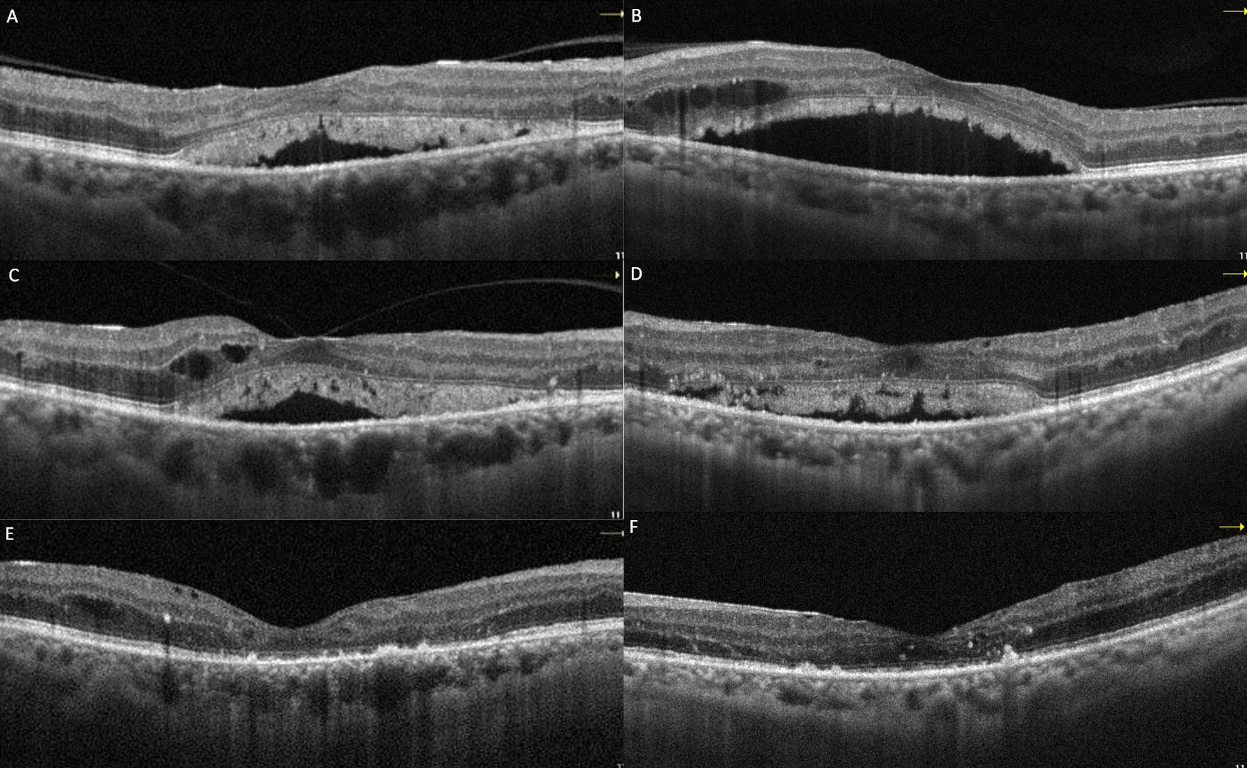

Following three intravitreal bevacizumab injections administered to both eyes, the patient’s BCVA declined to 20/100 in the right eye and 20/60 in the left eye. OCT images showed a decrease in intraretinal fluid, but there was no regression in SRDs (Figure 2A and B [Fig. 2]). Continuing panretinal photocoagulation was scheduled due to retinal ischemia on fundus fluorescein angiography (FFA) (Figure 2C and D [Fig. 2]). However, since the persistence of the SRD, no apparent leakage at the macula on FFA (Figure 2C and D [Fig. 2]), photoreceptor shedding was initiated on OCT (Figure 2A and B [Fig. 2]), and the patient complained of increased weakness and fatigue, an internal medicine consultation was requested. Laboratory tests showed hemoglobulin 6.8 g/dl (normal range: 13.1–17.2 g/dl), albumin 23 g/l (normal range: 35–52 g/dl), erythrocyte sedimentation rate 140 mm/h (normal value: <15 mm/h), C-reactive protein 14.9 mg/l (normal value: <6 mg/l) and hemoglobin A1c 8.1% (normal range: 3.5–5.7%) in the blood sample, and there was +3 proteinuria in the urine. Lymphadenopathy was also detected in the left inguinal region. Abdominal computerized tomography revealed lytic bone lesions in the left iliac wing, right acetabulum and L3–L4 vertebral bodies. The patient was diagnosed with multiple myeloma (MM) based on protein electrophoresis and hematologic examination. He was subsequently started on systemic chemotherapy for MM and no additional injections were administered for macular edema. Following initiation of treatment, macular subretinal fluid gradually resolved bilaterally (Figure 3A–F [Fig. 3]). The final OCT examination, 1 year after the first presentation showed resolution of the serous macular detachment (Figure 3E and F [Fig. 3]). At that time BCVA was 20/80 in the right eye and 20/100 in the left eye.

Figure 3: Macular OCT images of case 1 at 1 month (A: right, B: left), 3 months (C: right, D: left), and 1 year (E: right, F: left) after the initiation of systemic chemotherapy showed resolution of the subretinal fluid and shed photoreceptors.

At the patient’s first week follow-up after phacoemulsification surgery, the BCVA of the left eye showed no improvement. Macular OCT images revealed intraretinal and subretinal serous fluid accumulation (Figure 4A and B [Fig. 4]). At that time, laboratory tests showed a hemoglobulin A1c level of 12.1% (reference range: 3.5–6.7%), and a hemoglobin level of 13.6 g/dl (reference range: 12.6–17.4 g/dl). Due to DME, the patient was administered three monthly bilateral intravitreal bevacizumab injections and advised to improve glycemic control. However, the macular edema did not regress; on the contrary, it progressed (Figure 4C and D [Fig. 4]). Subsequently, the patient was lost to follow-up. One year later, ophthalmological examination revealed a BCVA of 20/200 in the right eye and counting fingers at 1 m in the left eye. Slit-lamp examination revealed bilateral pseudophakia, with mild posterior subcapsular opacification in the left eye. No signs of rubeosis iridis were observed. IOPs were within normal limits in both eyes. Fundus examination of the right eye disclosed extensive retinal hemorrhage, hard exudates, microaneurysms, and macular thickening. Visualization of the left fundus was not possible; however, ultrasonographic evaluation indicated findings consistent with intravitreal hemorrhage. Upon further assessment, it was revealed that the patient had been diagnosed with MM approximately one month earlier and had since initiated chemotherapy. At that time, the patient’s hemoglobin level was 11.7 g/dL (reference range: 13.2–16.6 g/dL), and hemoglobin A1c was 6.7% (reference range: 3.5–5.7%). The patient was advised to maintain an upright sitting position, and continue the systemic treatment.

Figure 4: Right (A) and left (B) macular OCT images of case 2 at the first week after left cataract surgery. While mild intraretinal edema was present in the right eye, there was marked subretinal serous fluid accumulation accompanied by intraretinal cysts in the left eye. After 3 monthly intravitreal bevacizumab injections, persistant subretinal fluid is visible in the right (C) and the left (D) eye.

Two months later, partial clearance of vitreous hemorrhage was observed (Figure 5A and B [Fig. 5]). Due to the presence of widespread retinal nonperfusion areas on FFA (Figure 5C and D [Fig. 5]), panretinal laser treatment was initiated. At that time, BCVA was 20/200 in the right eye and counting fingers at 2 m in the left eye. OCT demonstrated regression of macular edema in the right eye; however, hard exudates remained prominent, and disruption of the ellipsoid zone was noted (Figure 5E [Fig. 5]). The left eye remained difficult to visualize, although OCT findings suggested some resolution of the edema (Figure 5F [Fig. 5]). Approximately eight months after the initiation of systemic treatment, the hemorrhages in the right eye showed partial regression. Vitreous hemorrhage in the left eye had significantly cleared.

Figure 5: Color fundus (A, B), FFA (C, D) and macular OCT (E, F) images of case 2 at the second month following systemic chemotherapy. Capillary dropouts were noted in the right eye and in visible areas of the left eye in FFA. OCT shows regression of macular edema and disrupted ellipsoid zone on the right eye; the image quality of the left eye is poor, preventing a definitive assessment.